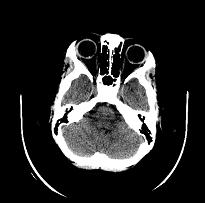

对该患者进行了急诊头颅CT扫描。CT显示右眼球靠近视神经处可见小片钙化,表明为小的视神经玻璃疣。左眼靠近视神经处也可见一小块边界不太清楚的区域,这也认为是更小的钙化灶,表明更小的视神经玻璃疣。(图2)